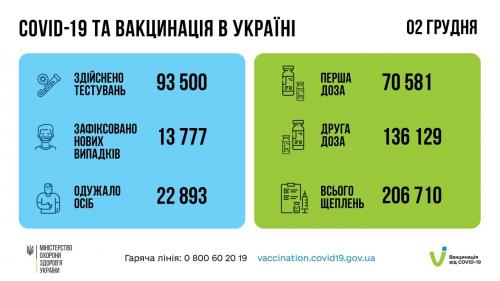

МОЗ: Уперше з початку пандемії було зроблено понад 100 тисяч ПЛР-досліджень за добу

19.11.2021 11:08